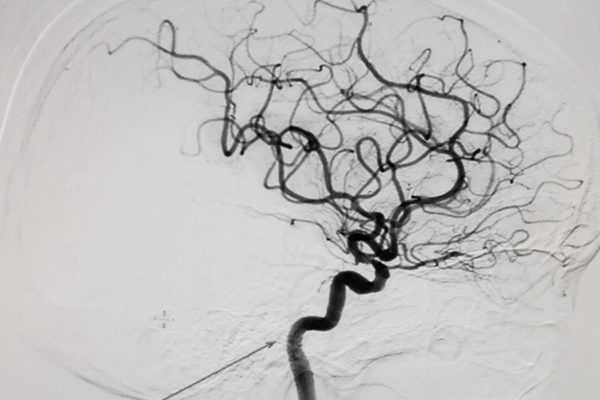

Chụp mạch số hóa xóa nền (DSA) là một phương pháp hình ảnh y khoa sử dụng kỹ thuật X-quang để quan sát mạch máu trong cơ thể. Kỹ thuật này tập trung vào việc tạo ra hình ảnh rõ nét của các mạch máu bằng cách loại bỏ các cấu trúc chắn bức xạ không cần thiết ra khỏi hình ảnh. Qua đó, bác sĩ có thể quan sát, đánh giá rõ ràng và chính xác tình trạng của các mạch máu, bao gồm cả các vấn đề như thuyên tắc, phình động mạch, hay các tắc nghẽn trong hệ thống mạch máu.

Chụp mạch số hóa xóa nền (DSA) là một kỹ thuật nội soi huỳnh quang, thường được sử dụng trong can thiệp X - quang để bác sĩ có thể quan sát chi tiết hình ảnh của các mạch máu trong cơ thể. Phương pháp này giúp loại bỏ các cấu trúc chắn bức xạ từ hình ảnh thông qua kỹ thuật số, từ đó tạo ra các hình ảnh rõ nét của mạch máu.

Kỹ thuật chụp DSA là sự kết hợp giữa việc xử lý hình ảnh bằng máy vi tính và quy trình chụp mạch máu theo phương pháp Seldinger. Trong quá trình chụp mạch máu số hóa xóa nền, nguyên lý cơ bản là sử dụng tia X và ánh sáng huỳnh quang để chụp mạch máu trước và sau khi bơm thuốc cản quang vào các vị trí cần kiểm tra. Máy tính sau đó loại bỏ hình ảnh nền, tạo ra một hình ảnh rõ ràng, chi tiết của các cấu trúc tim, động mạch cảnh, bụng, ngực, đùi - làm sáng tỏ hệ thống mạch máu. Điều này hỗ trợ bác sĩ phát hiện kịp thời các dấu hiệu không bình thường trong dòng máu, từ đó giúp chẩn đoán và điều trị chính xác các bệnh lý liên quan đến tuần hoàn máu trong cơ thể.